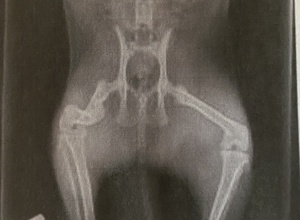

Für die Versorgung von Streunerkatzen richten wir teilweise auch kreisübergreifend Futterstellen ein. Wir versuchen, die Katzen einzufangen, um sie beim Tierarzt behandeln zu lassen (z.B. Versorgung von Verletzungen, Kastration, Entwurmung etc.).